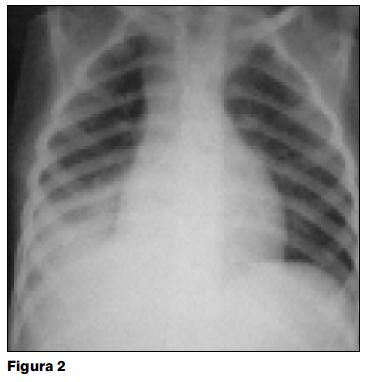

A los 8 días del alta reingresa por fiebre persistente. En la nueva radiografía persiste la consolidación parenquimatosa derecha y colapso total de los segmentos atelectasiados (figura 2). Durante esta internación presenta un acceso de tos cianozante, con crisis broncobstructiva severa. Este episodio, de breve duración, cede con oxigenoterapia y broncodilatadores. Al examen luego del episodio se destaca hipoventilación franca en la mitad inferior del hemotórax izquierdo. En la radiografía posterior a dicho episodio se observa hiperinsuflación del pulmón izquierdo con pulmonocele retroesternal y desplazamiento mediastinal contralateral, pulmón derecho sin imágenes de atelectasia ni consolidación parenquimatosa (figura 3).

En la evolución agrega acceso de tos cianozante con crisis broncobstructiva severa (episodio asfíctico), cambios en la auscultación y nueva radiografía posterior a dicho episodio con hiperinsuflación compensadora en pulmón izquierdo y desaparición de los elementos presentes en el pulmón derecho.